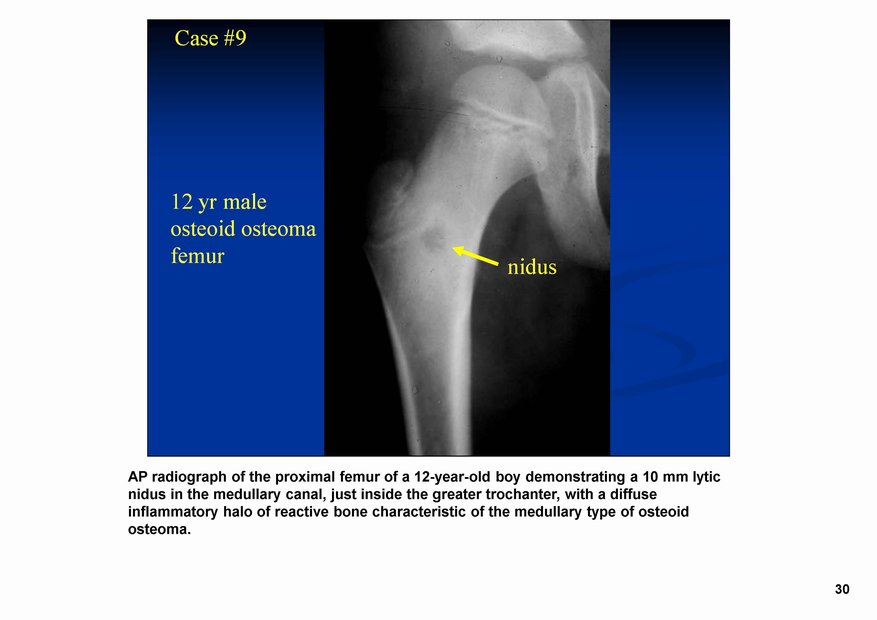

Остеоидная остема.

Диагностика и дифференциальная диагностика.